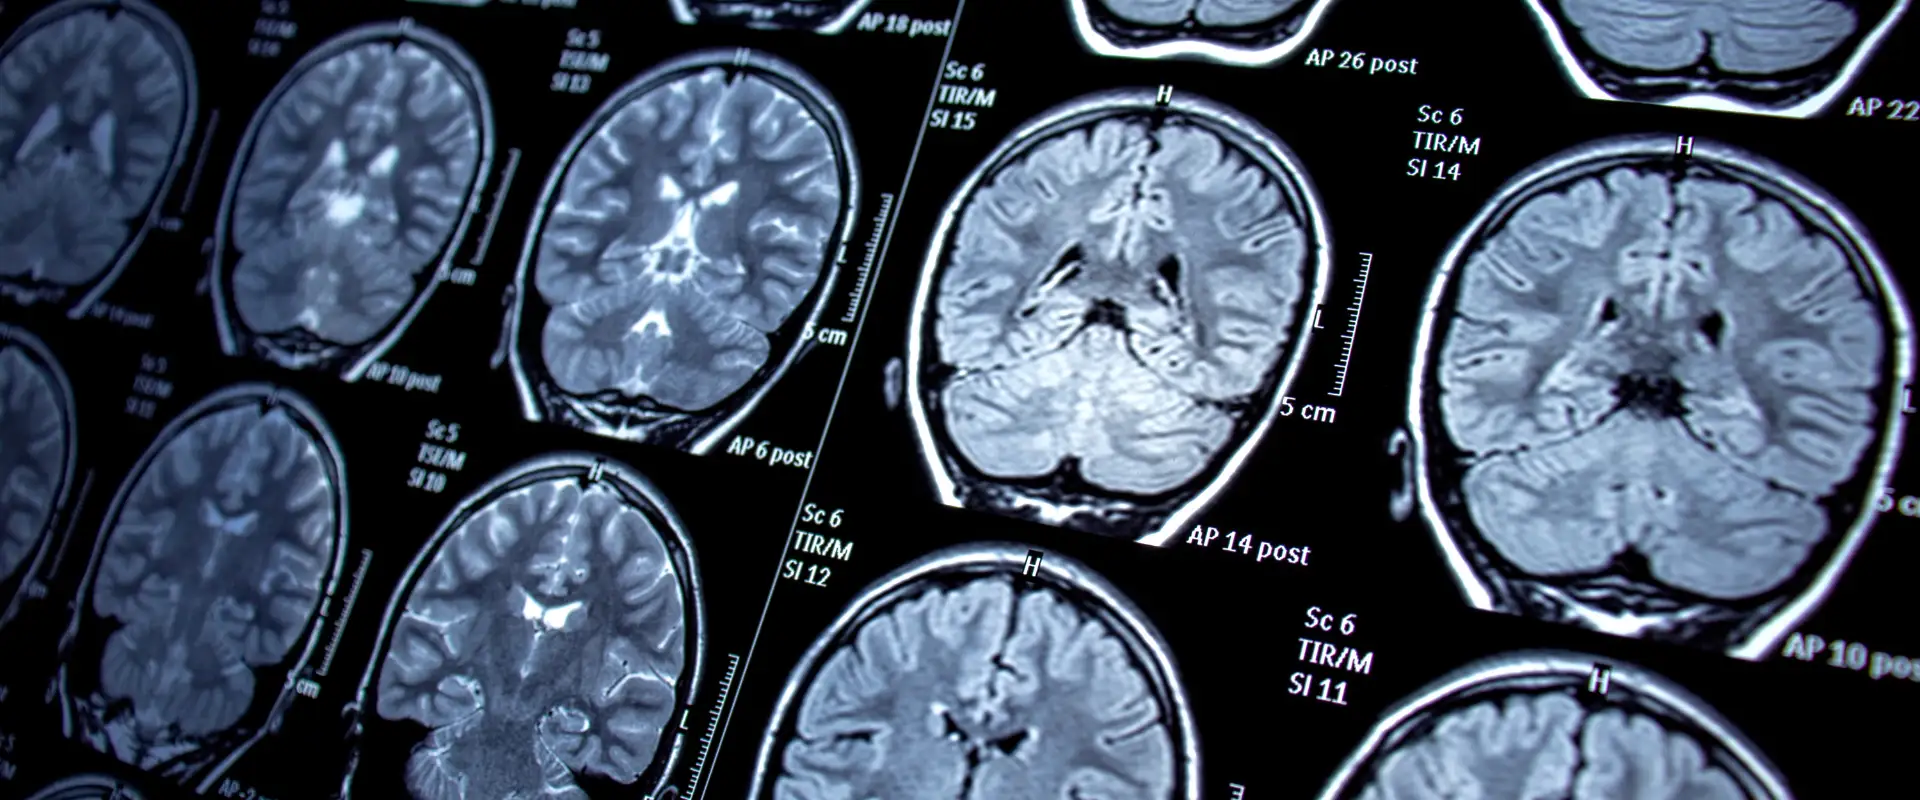

The Department of Neuro Surgery at Synergy Global Hospital provides advanced medical and surgical care for disorders of the brain, spine, and nervous system. Our expert neurosurgeons are trained in performing complex and delicate procedures using the latest technologies to ensure maximum precision, safety, and recovery.

We specialize in the diagnosis and treatment of brain tumors, spinal cord injuries, trauma, stroke, and nerve disorders. Our department is equipped with high-end neuro-imaging, operative microscopes, and minimally invasive techniques that allow faster rehabilitation and improved outcomes.